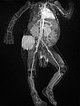

Dynamic contrast-enhanced MR angiography.

Starting in the early arterial phase, the tumor enhances intensively, although not completely.

The venous phase shows intense, homogeneous enhancement without immediate direct venous outflow.

In the late phase, the highly vascularized tumor continues to show strong enhancement without wash-out phenomenon.